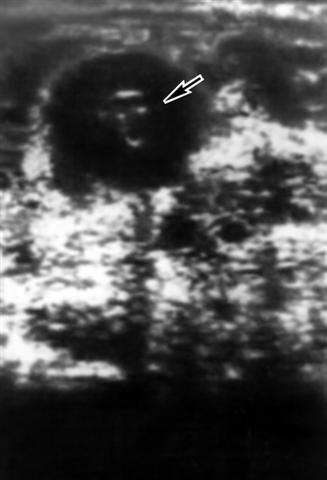

Рис. 7а). Патологический симптом «кокарды» при раке желудка: отмечается утолщение стенок пораженных органов (указаны стрелками), сужение их просвета.